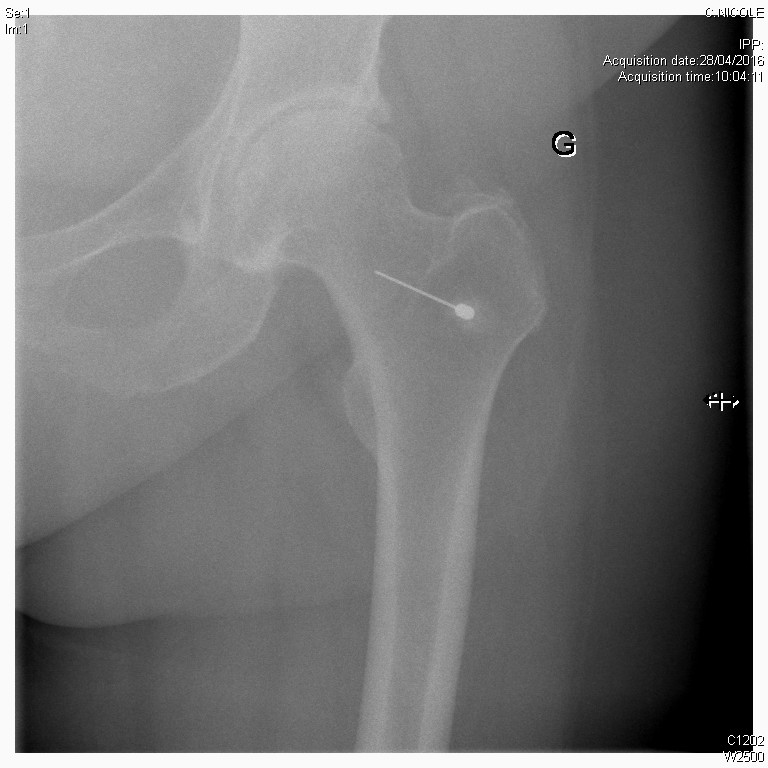

Scopie

Infiltration de la hanche sous contrôle scopique dans le cadre d'une coxarthrose